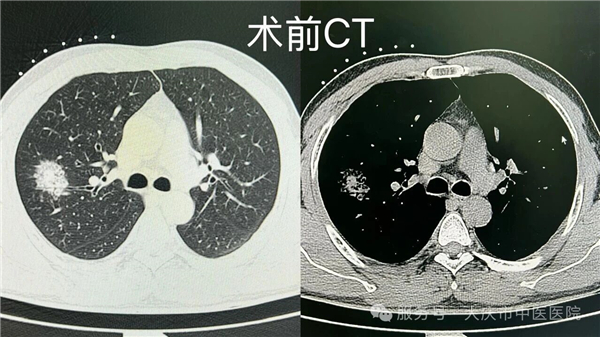

近日,在我院肺结节门诊牵头下,微创介入科联合 CT 室,成功开展一例肺结节同步病理活检与射频消融诊疗术。该技术在局部麻醉下,通过微创方式,同步完成病理活检取样与射频消融治疗,术中患者生命体征平稳,术后恢复良好。

传统肺结节诊疗通常分两步:先穿刺活检,等待3-5天病理报告,待病理结果回报后,再根据病情制定后续治疗方案,这不仅拉长住院周期,两次穿刺也增加了气胸、出血等风险。

本次开展的同步诊疗技术,在 CT 精准定位下,通过消融针到达病灶区域实施消融治疗,并通过同一通道获取组织标本进行病理检查,实现诊断与治疗环节的紧密衔接,有助于缩短诊疗周期,减少多次操作可能带来的相关风险。该技术的成功开展,是我院多学科协作及学科群建设的一次实践,为肺结节诊疗提供了新的技术选择。